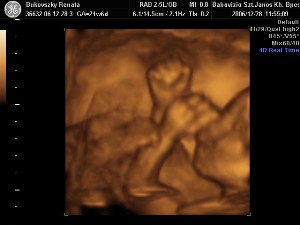

a bal szeme előtt a bokája van

a bal szeme előtt a bokája van

a lába mindig az arca előtt van

a lába mindig az arca előtt van